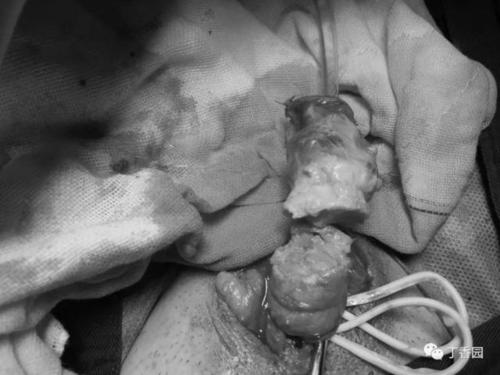

切开睾丸手术全过程

切开睾丸手术全过程,睾丸切除术手术图片

男孩左侧睾丸坏死,接受手术切除

睾丸切除术手术图片